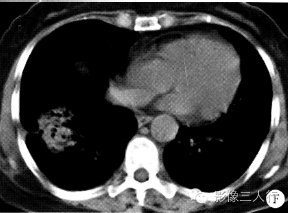

图A〜E为CT肺窗,图F为纵隔窗。两肺外围散在性分布斑片状模糊影,跨叶、段分布。其中两肺上叶、左下叶以磨玻璃样密度为主,右肺下叶病灶密度较高,以实变为主,病灶似呈团块状,可见支气管气相、肺泡含气征及索条影,与邻近胸膜有牵拉。两肺门周围肺野未见明显异常。与3周前外院CT 片比较,病灶有一定的游走性(图略)。

两肺非节段性分布的炎性改变伴血常规嗜酸性粒细胞明显增高,实验室多种寄生虫抗原、抗体检测均阴性。抗过敏治疗1周无效。临床会诊后考虑“慢性嗜酸性粒细胞肺浸润”。对症治疗3个月后复查CT示两肺病灶基本吸收(图G〜I)。

嗜酸性粒细胞肺浸润典型的影像表现为两肺非节段性、广泛分布、互相融合的肺泡和间质的实变,多为周围性胸膜下分布,肺门周围较少受累。磨玻璃影多分布在上、中肺野,常为一过性和迁徙性,胸膜下有带状线。在本病例中,我们注意到了病灶的游走性,而忽略了肺间质的改变。但大部分嗜酸性粒细 胞肺浸润的CT表现并无特异性,而且与多种疾病的表现有相当的重叠。因此,有文献认为,在对每一个嗜酸性粒细胞肺浸润病例作出诊断时,还是要密切结合临床才能取得准确的诊断结果。 医学百科网 | YxBaike.Com